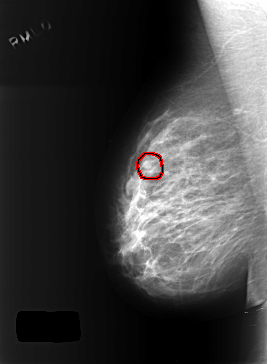

ics_version 1.0 filename C-0402-1 DATE_OF_STUDY 9 1 1996 PATIENT_AGE 49 FILM FILM_TYPE REGULAR DENSITY 2 DATE_DIGITIZED 15 10 1998 DIGITIZER LUMISYS LASER SEQUENCE LEFT_CC LINES 5552 PIXELS_PER_LINE 4056 BITS_PER_PIXEL 12 RESOLUTION 50 NON_OVERLAY LEFT_MLO LINES 5440 PIXELS_PER_LINE 3984 BITS_PER_PIXEL 12 RESOLUTION 50 NON_OVERLAY RIGHT_CC LINES 5640 PIXELS_PER_LINE 3800 BITS_PER_PIXEL 12 RESOLUTION 50 OVERLAY RIGHT_MLO LINES 5448 PIXELS_PER_LINE 4000 BITS_PER_PIXEL 12 RESOLUTION 50 OVERLAY |

FILE: C_0402_1.RIGHT_MLO.OVERLAY TOTAL_ABNORMALITIES 1 ABNORMALITY 1 LESION_TYPE MASS SHAPE OVAL MARGINS CIRCUMSCRIBED ASSESSMENT 3 SUBTLETY 4 PATHOLOGY BENIGN TOTAL_OUTLINES 1 BOUNDARY |